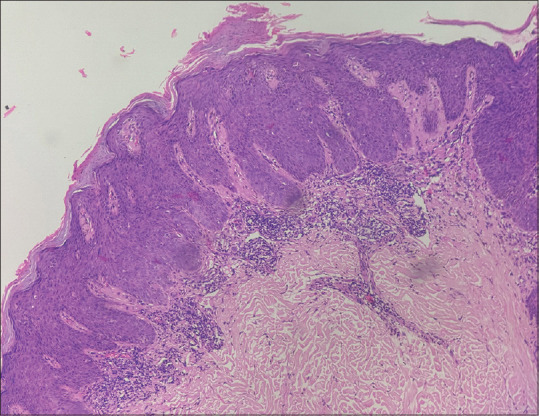

Abstract: Benign lichenoid keratosis (BLK), also known as lichen planus-like keratosis, is a benign cutaneous lesion of unknown etiology with overlapping clinical and dermoscopic features with malignant lesions. A 52-year-old female presented with a 10- years history of a single asymptomatic lesion on the left gluteal region not associated with loss of weight, loss of appetite, or other systemic symptoms. Clinical examination revealed a single well-defined violaceous to hyperpigmented plaque of approximately 4 cm × 3 cm in size, on the lateral aspect of the left gluteal region. Dermoscopic examination showed overlapping features of BLK and melanoma. Ultraviolet (UV)dermoscopy showed 'dermoscopic UV blink sign' and areas of blue, yellowish-green, and red fluorescence. Histopathological examination showed features suggestive of BLK with no cellular atypia. The patient was started on 5% imiquimod cream 5 days a week and advised to follow up. This case emphasizes the importance of clinical, dermoscopic, UV reflectance dermoscopic, and histopathological correlation in establishing the diagnosis of BLK masquerading as melanoma with regression, thus aiding in the avoidance of unnecessary surgeries.